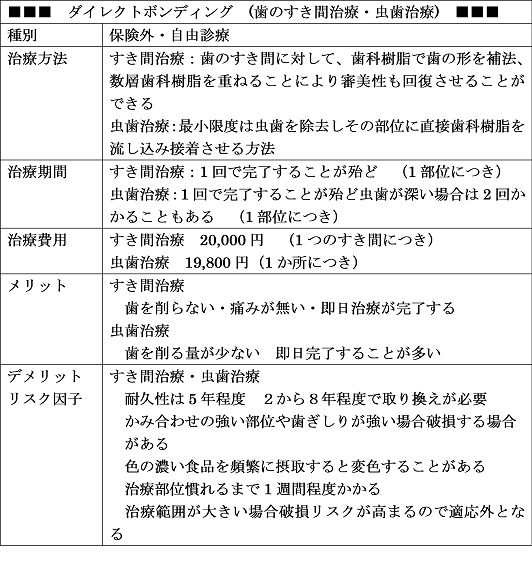

歯のすき間を治す ダイレクトボンデング

治療法:ダイレクトボンディング

利点 歯を殆ど削らない、基本的に1回で1つのすき間の治療可能

矯正やセラミックに比べ低費用

欠点 一生持つものではなく、数年で(2年から5年)で修正や再治療の必要がある

ダイレクトボンディング

歯のすき間を治す方法には

①歯列矯正

②セラミック修復 (歯を削りセラミックの歯をかぶせる)

③ダイレクトボンディング

があります。どの方法も利点欠点があります。

①②③の利点と欠点

①費用5万〜20万・期間は数か月〜1年・歯を削らずに治療可能 ・食事制限なし

②費用6万〜16万・期間は2から3回 ・歯を削る必要あり ・食事制限なし

③費用2万〜3万 ・期間は2回 ・歯を削る必要なし ・食事制限あり

硬いものを食べることや前歯で噛み千切る等をすると割れることがある。